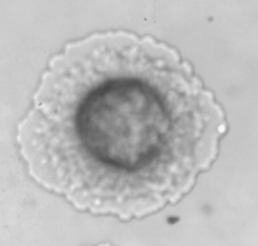

Introduction. One of the more promising developments in preventing the spread of infections, including COVID-19, is the production of vaccines based on virus-like particles (VLP). Currently, in the National Research Center for Epidemiology and Microbiology named after N.F. Gamaleya of the Ministry of Health of the Russia has developed a VLP-based vaccine against COVID-19.